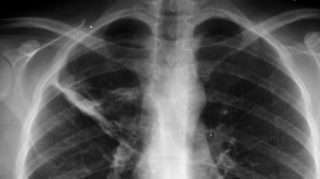

Una donna di 27 anni è stata curata per mesi con farmaci anti-tubercolosi, con scarsi risultati, salvo poi scoprire di avere un preservativo incastrato nei polmoni. No, non è una bufala. A riportare l’episodio è stato il portale National Library of Medicine. Un caso limite ma, a quanto pare, possibile che è stato quindi descritto in maniera dettagliata sul portale online della più grande biblioteca medica al mondo.

Secondo quanto riportato, la donna si è presentata in ospedale con tosse e febbre accusando un muco denso e persistente da mesi. Dopo antibiotici e trattamenti anti-tubercolosi, la 27enne si è rivolta di nuovo ai medici. Un attento esame del torace e una radiografia hanno permesso di individuare una lesione nel lobo superiore destro dei suoi polmoni, che, descrivono i medici, sembrava simile a una “borsa rovesciata” seduta “nel bronco”. Solo un’operazione di rimozione della misteriosa “borsa” ha però potuto svelare cosa fosse l’oggetto che causava la lesione: un preservativo.